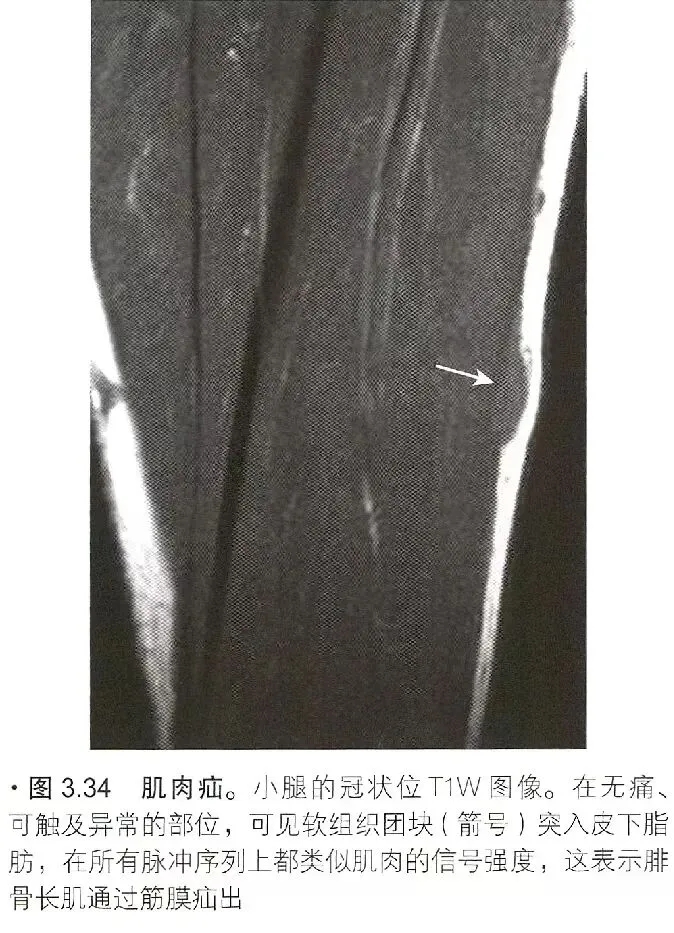

肌疝